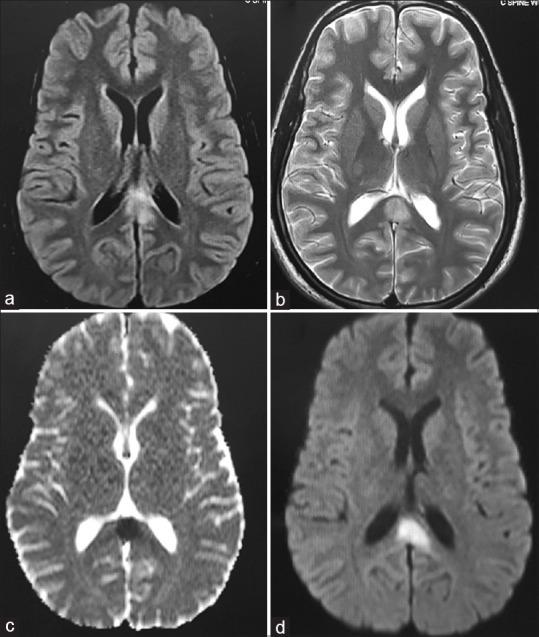

Isolated Infarction of the Splenium: A Rare Presentation of Mild Head Injury.

Posttraumatic cerebral infarction (PTCI) is a devastating complication of traumatic brain injury. It is usually seen in patients with moderate-to-severe head injury with a reported incidence of 1.9%-10.4%. Brain shift associated with the traumatic intracranial space-occupying lesions with or without severe cerebral edema is the most common mechanism underlying the PTCI. Without associated direct vascular injury, isolated PTCI is very rare after mild head injury. Such cases of PTCI following mild head injury have been reported in children in whom they usually affect the gangliocapsular region supplied by the lenticulostriate arteries. Such infarcts in adults are extremely rare. Although the exact pathogenesis is not clear, vasospasm or shearing-associated intimal tear is proposed to be the cause for this infarct. Other common causes of cerebral infarction should be ruled out before making such a diagnosis. Unlike PTCI associated with a severe head injury, cerebral infarction following mild head injury is expected to have a better neurological outcome.